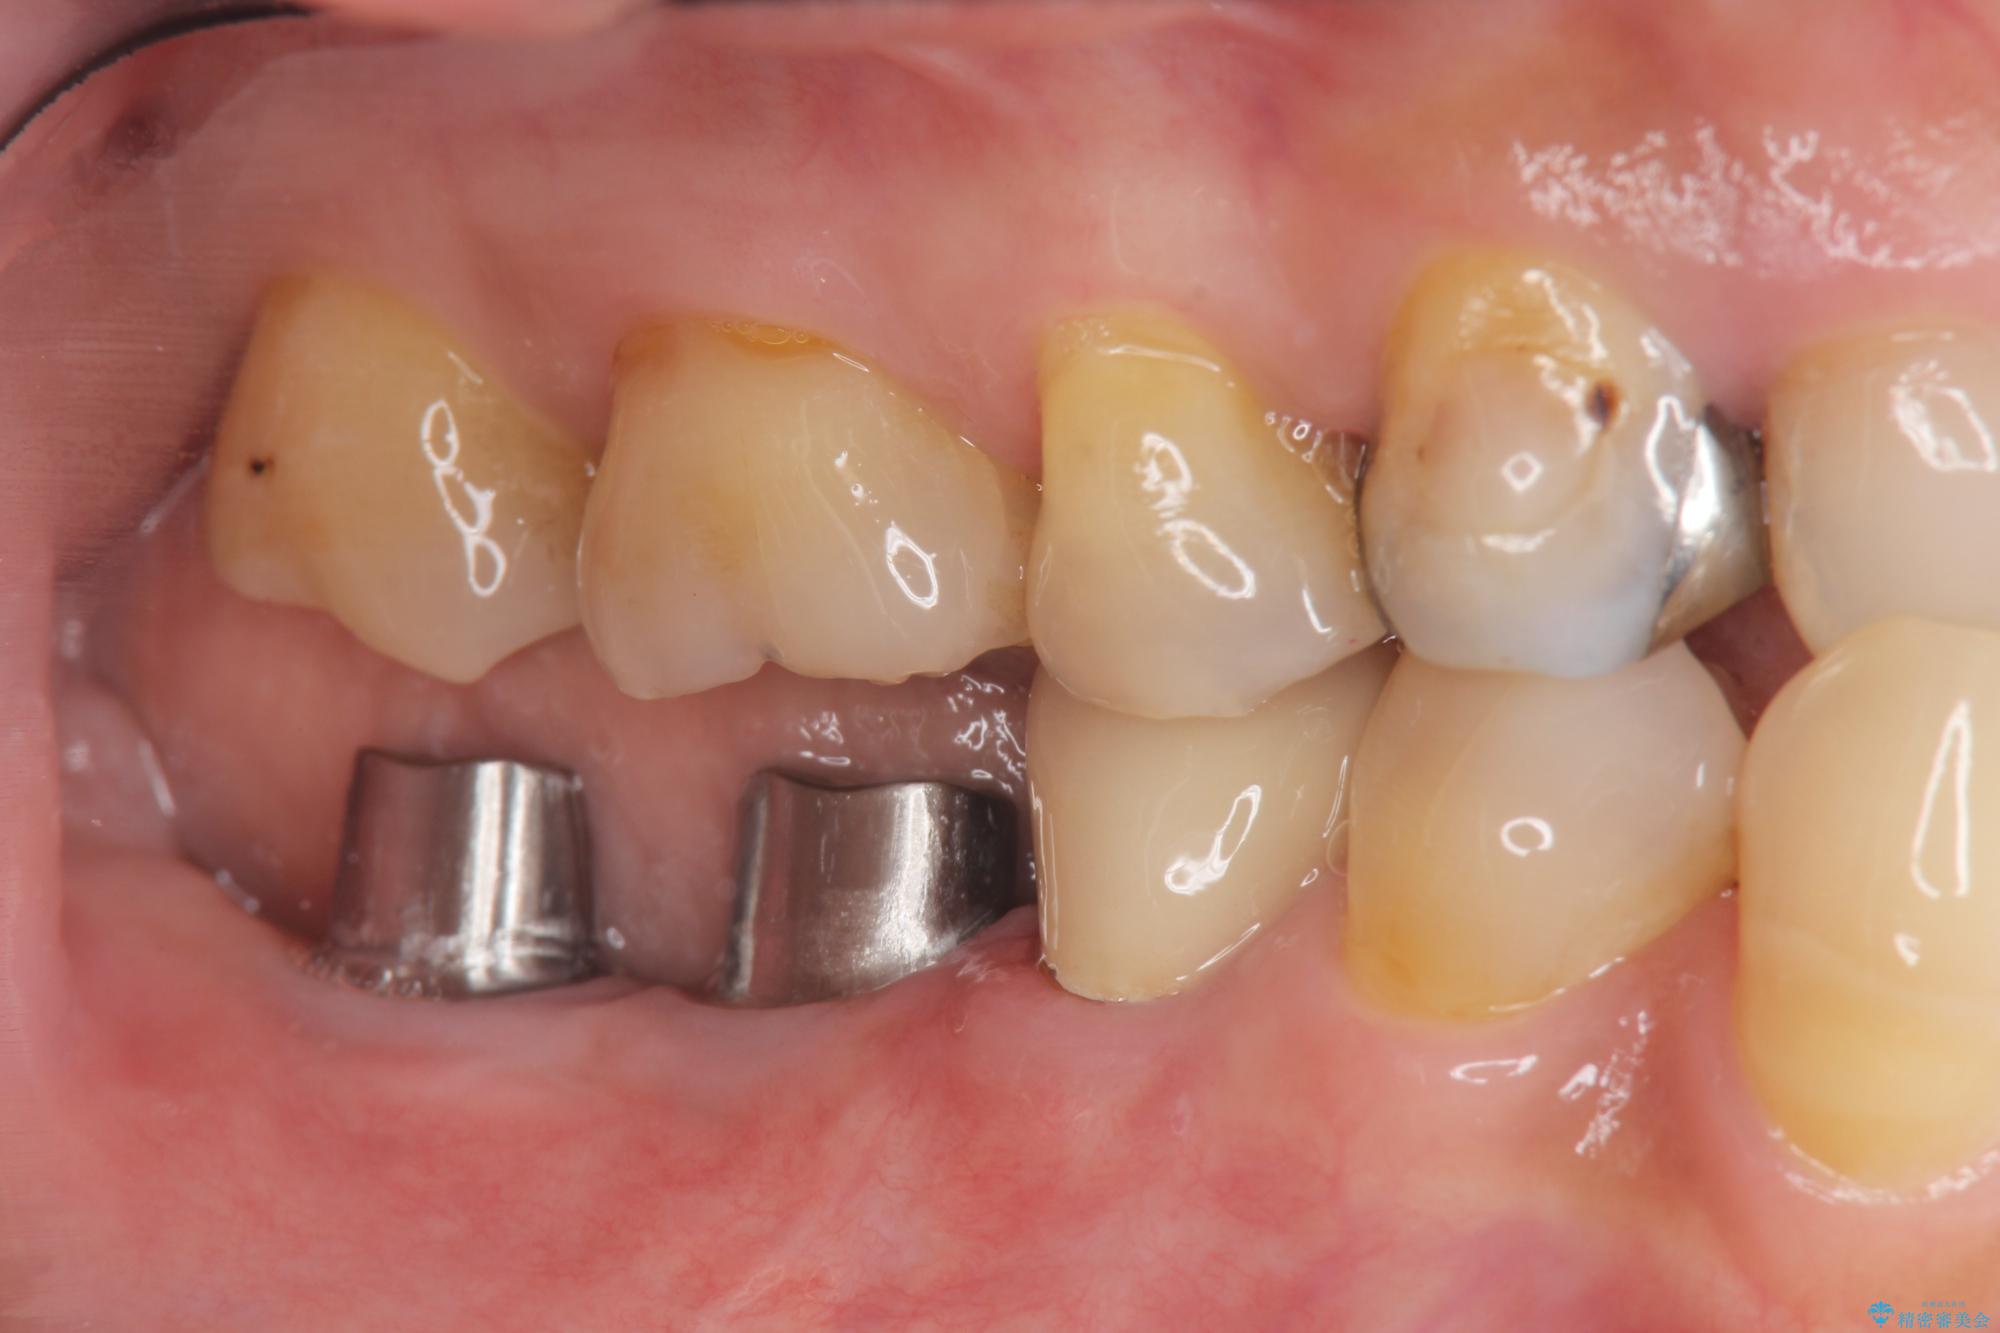

治療前

奥歯から膿のにおいがする インプラントによる機能回復 治療前画像 奥歯から膿のにおいがする インプラントによる機能回復 治療前画像 奥歯から膿のにおいがする インプラントによる機能回復 治療前画像 奥歯から膿のにおいがする インプラントによる機能回復 治療前画像 奥歯から膿のにおいがする インプラントによる機能回復 治療前画像 奥歯から膿のにおいがする インプラントによる機能回復 治療前画像

治療中

奥歯から膿のにおいがする インプラントによる機能回復 治療中画像 奥歯から膿のにおいがする インプラントによる機能回復 治療中画像 奥歯から膿のにおいがする インプラントによる機能回復 治療中画像 奥歯から膿のにおいがする インプラントによる機能回復 治療中画像